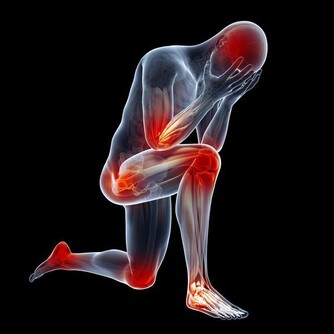

當我們的腎臟出現問題時,我們的身體會出現一些症狀,

這時,如果大家忽視這些症狀,就有可能早晨腎臟更為嚴重的病變。

下面小編給大家總結了一些關於腎臟出現問題時,我們身體出現的反應,希望大家及時發現問題,及時治療。

1 、聽力清晰:在中醫理論中,耳朵的聽覺功能與腎氣的盛衰密切相關,腎好聽力就好。

反之,當出現耳鳴、心煩、聽力下降的症狀時,可以多考慮腎陰虛。

2、皮膚有光彩:腎好,才能青春常駐,延緩衰老。腎不好,人容易顯得蒼老,皮膚會變得晦暗,膚色也會發生變化,眼眶發黑,眼袋明顯。

3、頭髮烏黑:腎藏精,其華在發,發的營養來源於血,但其生機根本還在於腎,腎不好,頭髮會早發白、失去光澤,並且出現脫髮。

4、骨骼強壯:中醫認為,腎主骨,骨靠腎精滋養,腎好骨才好。腎氣衰敗會出現骨質疏鬆、腰酸背痛,甚至牙齒出現鬆動。

5 、記憶力好:腎精也養大腦。因此腎不好可能會出現經常忘事、反應遲鈍等現象。

6 、尿液清澈泡沫少:若小便泡沫突然變多,長時間不消失,說明尿液中排泄的蛋白質較多;若尿液顏色異常,呈濃茶色、醬油色或混濁如淘米水時,都應引起重視。另外,出現憋不住尿、小便疼的症狀也應及時就診。

7、早起身體沒有浮腫:腎臟是人體代謝水分的器官,腎不好,水分就會蓄積。如果經常早起眼皮浮腫,或者雙腳、雙腿浮腫,都要考慮腎臟問題。

8、精神十足:當腎功能出現問題時,身體裡的廢物殘渣難以從尿液裡排泄出去,會出現精神不振、疲勞、沒勁兒的感覺。